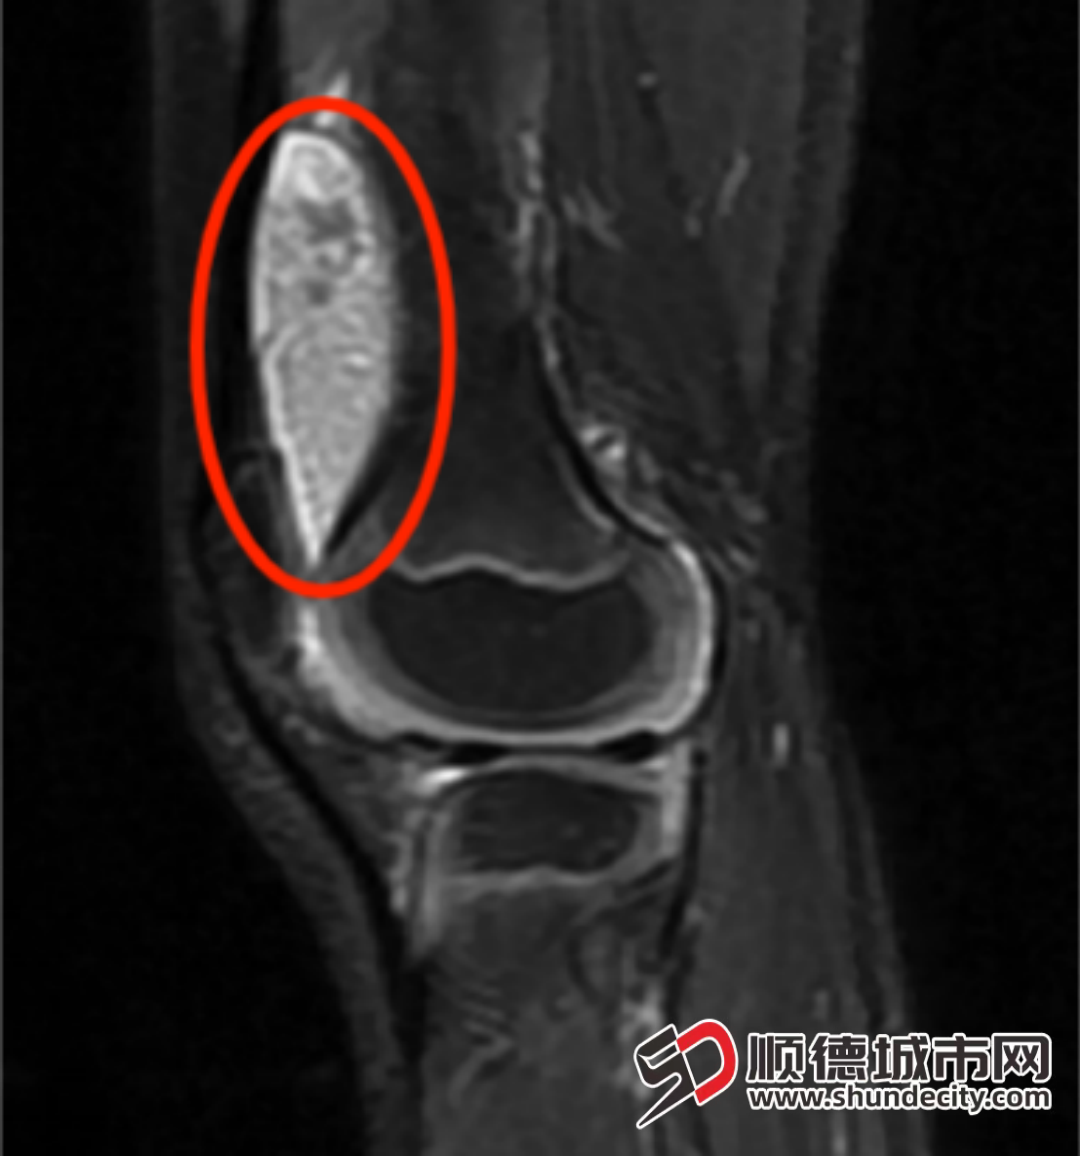

膝关节MRI影像可见密密麻麻的滑膜组织。

经全面评估,“米粒体滑膜炎”的诊断最终明确。征得家属同意后,手术团队为可可实施微创治疗。术中,王福科主任先通过穿刺取出部分病变组织,当一粒粒黄白色、米粒大小的组织被吸出时,此前的诊断得到印证。随后,团队借助关节镜技术,仔细清除了关节内所有“小米粒”样病变组织。